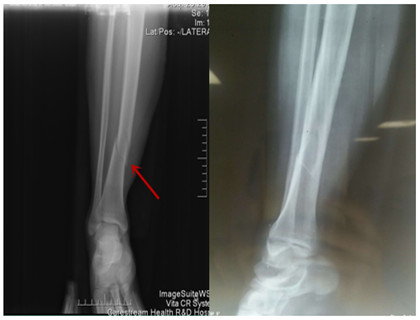

我院首例脛骨骨折MIPPO技術(shù)